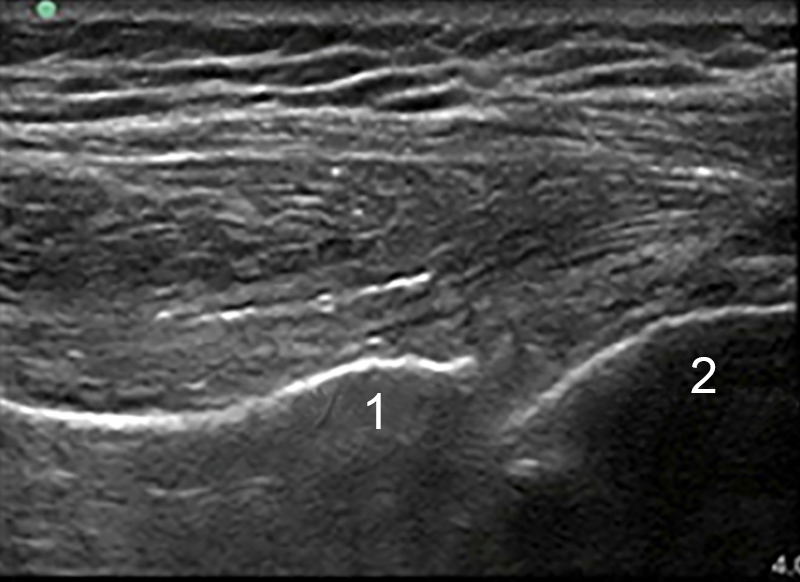

无 MBe 的肩部后盂肱注射图像

MBe 技术关闭的盂肱骨关节注射

关节窝

肱骨头